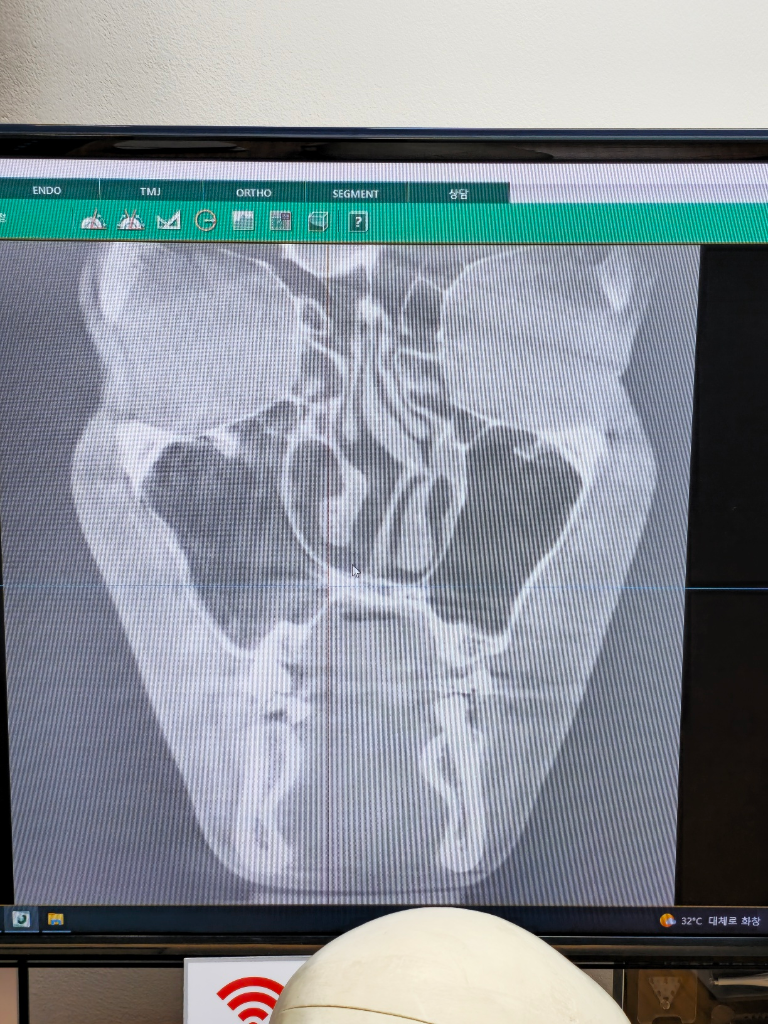

비중격만곡증때문에 기능코수술 했는데 잘된걸까요?

안녕하세요 제가 2달전에 코에 문제가 좀 있어서 이비인후과를 갔다가 코 모양이 심하게 안좋다고 큰병원 가서 성형하는게 어떻냐는 얘기를 듣고

신사동의 성형외과에서 기능코수술과 미용코 수술을 둘다 했습니다.

미용코 같은경우는 제가 유전적으로 코가 심한 매부리코여서 추가적으로 한거구요

숨 쉬는데 수술전과 큰 차이가없어서

수술전이랑 다르게 CT사진을 좀 자세히는 안보여주더라구요

그래서 혹시 수술 전후 차이가 별로 없는거 아닐까 싶어서 질문드립니다

위 두 사진은 수술 전 CT구요

이건 수술 후 CT

이건 모양변화입니다 어때보이나요?

CT 는 전체적으로 입체적으로 볼 수 있는 검사로, 해당 한 단면만으로는 판단이 어렵습니다. 추후 코막힘 등 증상이 지속된다면 병원 재방문해보시면 되겠습니다.